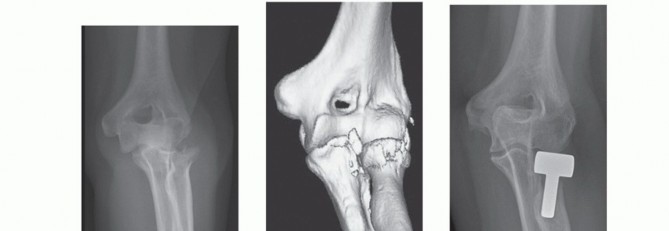

Patients who are known to have, or are likely to have, an associated ligamentous injury of the elbow or forearm should have a radial head arthroplasty because radial head excision is contraindicated (FIG 2).29

FIG 2 • A,B. AP and lateral radiographs of a 54-year-old woman who sustained a posterolateral elbow dislocation associated with a comminuted fracture of the radial head and coronoid—the “terrible triad.” C,D. Preoperative 3-D reconstruction images demonstrating a comminuted radial head fracture with a small undisplaced coronoid fracture. E,F. Postoperative radiographs after modular radial head arthroplasty (Evolve, Wright Medical Technology, Arlington, TN) and repair of the lateral collateral ligament. Medial collateral ligament and coronoid repairs were not required because the elbow was sufficiently stable at the end of the procedure. A good functional outcome was achieved at the final follow-up.*